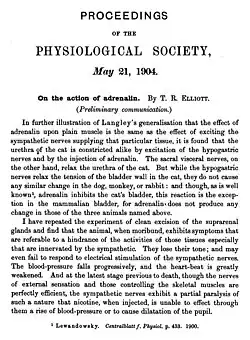

A new chapter was opened when Max Lewandowsky in 1899 in Berlin observed that adrenal extracts acted on the smooth muscle of the eye and orbit of cats—such as the iris dilator muscle and nictitating membrane—in the same way as sympathetic nerve stimulation.[27] The correspondence was extended by John Newport Langley and, under his supervision, Thomas Renton Elliott in Cambridge. In four papers in volume 31, 1904, of the Journal of Physiology Elliott described the similarities organ by organ. His hypothesis stands in the abstract of a presentation to the Physiological Society of May 21, 1904, a little over ten years after Oliver and Schafer's presentation:[28] "Adrenalin does not excite sympathetic ganglia when applied to them directly, as does nicotine. Its effective action is localized at the periphery. I find that even after complete denervation, whether of three days' or ten months' duration, the plain muscle of the dilatator pupillae will respond to adrenalin, and that with greater rapidity and longer persistence than does the iris whose nervous relations are uninjured. Therefore, it cannot be than adrenalin excites any structure derived from, and dependent for its persistence on, the peripheral neurone. ... The point at which the stimulus of the chemical excitant is received, and transformed into what may cause the change of tension of the muscle fiber, is perhaps a mechanism developed out of the muscle cell in response to its union with the synapsing sympathetic fiber, the function of which is to receive and transform the nervous impulse. "Adrenalin" might then be the chemical stimulant liberated on each occasion when the impulse arrives at the periphery." The abstract is the "birth certificate" of chemical neurotransmission.[29] Elliott was never so explicit again. It seems he was discouraged by the lack of a favorable response from his seniors, Langley in particular, and a few years later he left physiological research.

- The 'birth certificate' of chemical neurotransmission

-

-